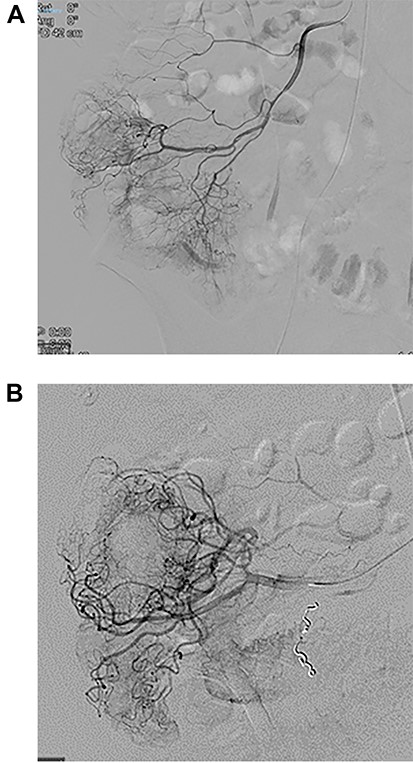

At angiogram, the superior mesenteric artery (SMA) was successfully cannulated, and the patient was found to have active extravasation from the appendiceal artery (Fig. 2). This was successfully controlled with a 3 mm coil.

Images from angiography. (A) Pre-embolization, demonstrates appendiceal lumen filled with contrast. (B) Demonstrated coiled artery.